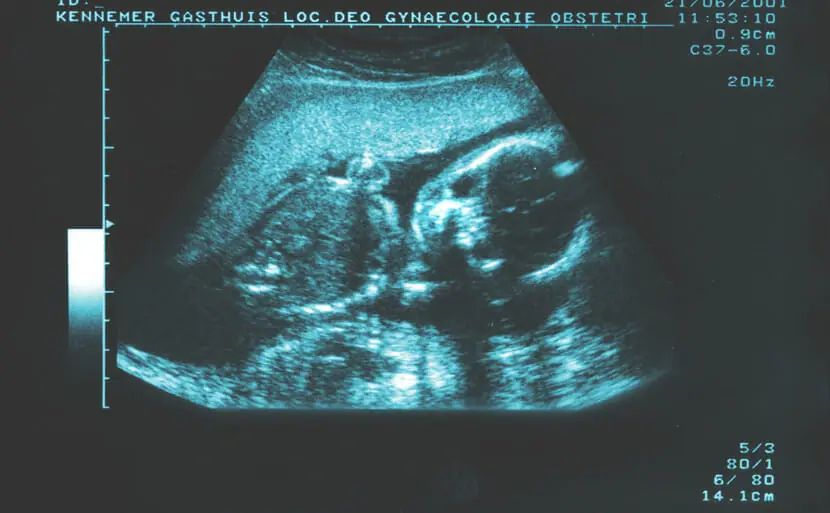

エコーで21トリソミー(ダウン症候群)が分かる場合もあります

妊娠中に行うエコー検査(超音波検査)で21トリソミー(ダウン症候群)の胎児の特徴を発見できる場合があります。21トリソミー(ダウン症候群)の胎児は血流が悪いため、首の後ろにむくみが出ることが多いためです。このむくみをNT(Nuchal Translucency)といい、通常妊娠11週から13週に計測することができます。

首の後ろのむくみ以外にも特有の特徴があります。

顔に見られる特徴の一つは鼻です。鼻の骨がない、鼻の骨が薄い、鼻の骨の成長に遅れがあるなどの特徴が見られます。

また、体の特徴では、手足の長さが基準より短い、心臓の病気がある(三尖弁逆流・静脈管逆流)、頭が大きいなどの所見があると、21トリソミー(ダウン症候群)の胎児である可能性があります。

顔や体の特徴を細かく見ていく必要があるので、通常の妊婦検診で用いられる2Dエコーよりも、4Dエコーの方が、発見しやすいと言えます。心配な場合は、4Dエコーが見られる産院でみてもらうと良いでしょう。

エコーで21トリソミー(ダウン症候群)が分かる確率

エコーによって、21トリソミー(ダウン症候群)の特徴を発見できることは多いですが、胎児の位置などによっては明確にわからないこともあります。また、所見があっても21トリソミー(ダウン症候群)によるものではないこともあります。そのため、どのくらいの確率で21トリソミー(ダウン症候群)がわかるとは定義することはできません。

エコーで21トリソミー(ダウン症候群)が分かる時期はいつ(何週目)?

エコーで21トリソミー(ダウン症候群)の所見が観察できるようになるのは、おおむね妊娠11週以降です。

しかし、エコーは確定的診断方法ではないため、受けていても妊娠中に21トリソミー(ダウン症候群)だと指摘されない、わからなかったという場合もあります。